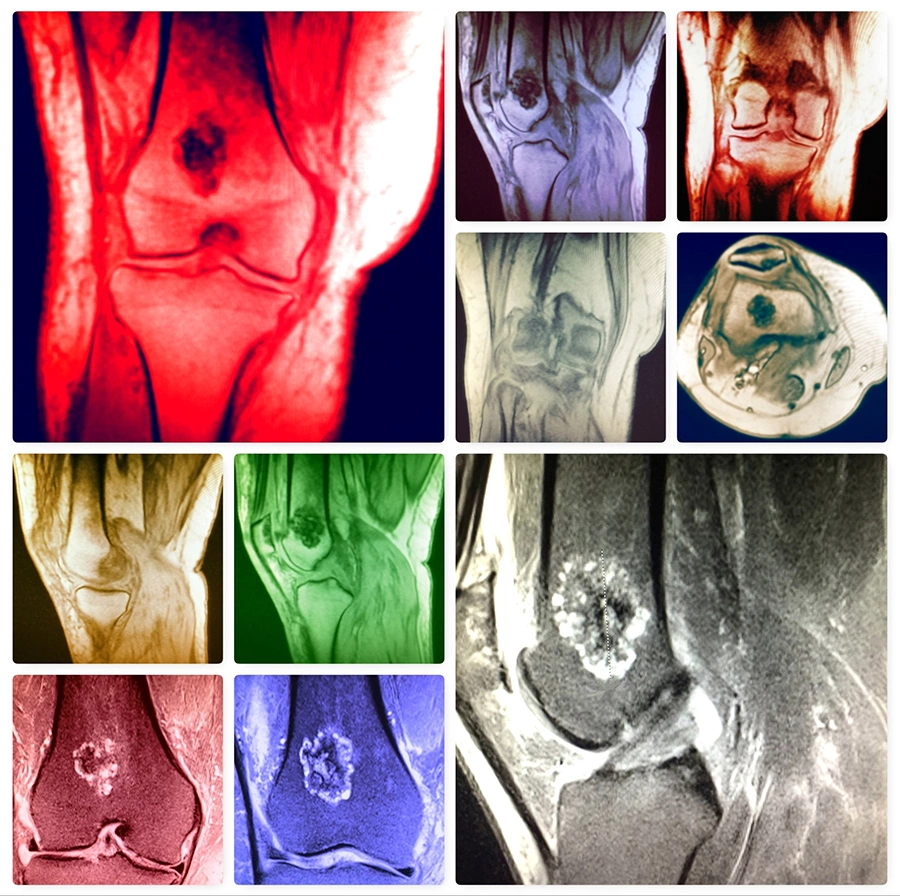

- рентгенография — на снимках видна только энхондрома, для обнаружения периферического новообразования необходимы высокотехнологичные методики;

- КТ — подходит для визуализации опухолей в труднодоступных местах (околоносовые пазухи, основание черепа и ряд других);

- МРТ — самый информативный метод диагностики, позволяет выявить все виды хондром;